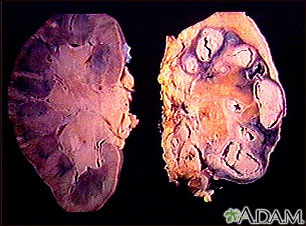

Pulmonary tuberculosis (TB) is a contagious bacterial infection that involves the lungs. It may spread to other organs.

Pulmonary TB is caused by the bacterium Mycobacterium tuberculosis (M tuberculosis). TB is contagious. This means the bacteria may spread from an infected person to someone else. You can get TB by breathing in air droplets from a cough or sneeze of an infected person. The resulting lung infection is called primary TB.

Pulmonary TB can cause permanent lung damage if not treated early. It can also spread to other parts of the body.